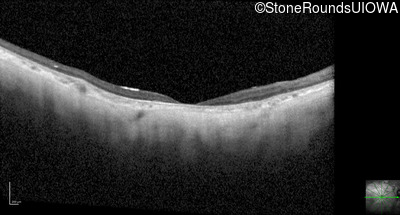

Optical Coherence Tomography - Right - 10/200 sc

Exemplar / OCT Stack

OCT Stack